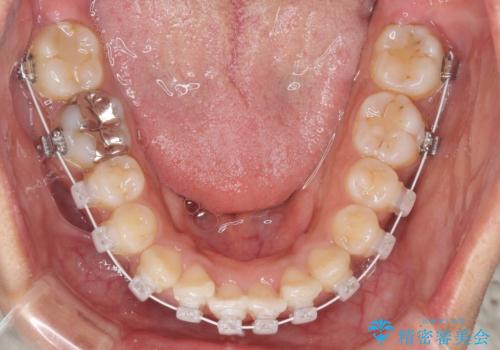

- インビザライン・審美装置

当初はインビザラインにて治療を開始しましたが、自己管理による治療が難しくなり、ワイヤー矯正へ転換して継続しました。

2年ほどインビザライン矯正を続けましたが、終了することができず、ワイヤーへ転換後は1年弱で終えることができました。